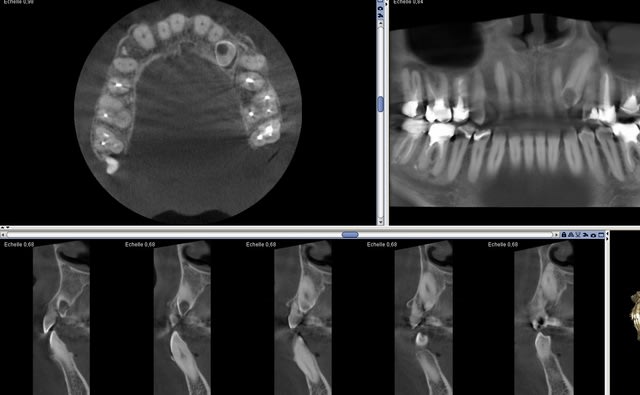

Canine incluse cariée nécrosée qui a provoqué un bel abcès. Patient la cinquantaine. Vraiment pas de bol :)))))

Saloperie de crochet apical, même avec le piézo j'ai du faire un cratère, j'en connais un qui doit apprécier son ixprim ce soir.